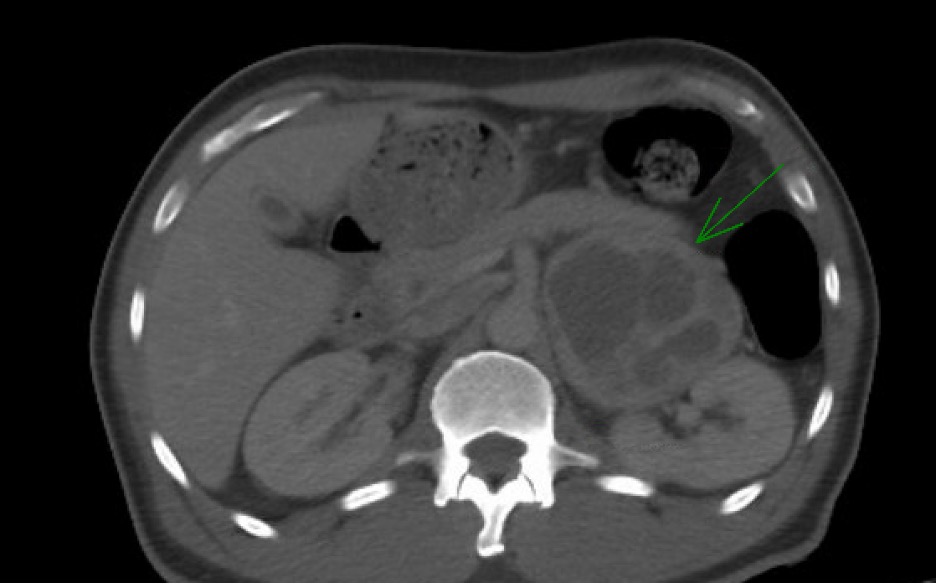

Case Presentation: A 56-year-old man with type 2 diabetes and hypertension presented to the ER with uncontrolled blood sugars, intermittent nausea, vomiting, fevers, and a 15-pound unintentional weight loss over one month. He was recently hospitalized with similar symptoms, started on insulin, and evaluated for fevers with negative blood and urine cultures, which were attributed to a viral illness. At presentation, labs showed severe hyperglycemia, leukocytosis, elevated creatinine, and troponin, but infectious testing including urinalysis and chest X-ray was again unremarkable. A transthoracic echocardiogram revealed diffuse left ventricular hypokinesis with an ejection fraction of 40-44%, prompting initiation of metoprolol. Despite increasing insulin, hyperglycemia persisted. A CT scan of the abdomen and pelvis was performed to evaluate for malignancy, revealing a solid cystic mass in the left adrenal gland measuring 8 x 7 x 9.3 cm. The patient developed hypertensive crises with systolic BP reaching 200 mmHg, alternating with orthostatic hypotension, requiring IV fluids. Suspecting pheochromocytoma, metoprolol was discontinued and phenoxybenzamine was started. Biochemical tests confirmed pheochromocytoma with elevated plasma metanephrine (950 pg/mL), urine metanephrine (7614 mcg/g creatinine), and plasma normetanephrine (875 pg/mL). He underwent left adrenalectomy and nephrectomy due to left renal vein involvement. Postoperatively, his glucose normalized, fevers resolved, and insulin was discontinued. Pathology confirmed the diagnosis of pheochromocytoma.